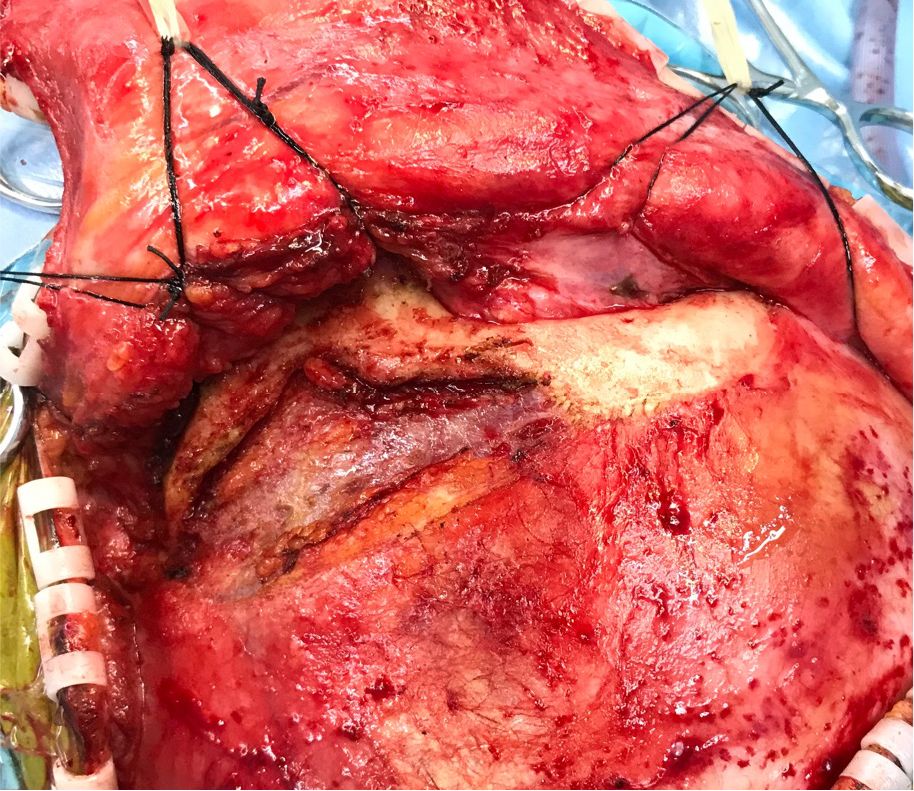

筋膜间分离、暴露颧弓。

![]()

游离颧弓,翻起颞肌。

额颞瓣开颅。